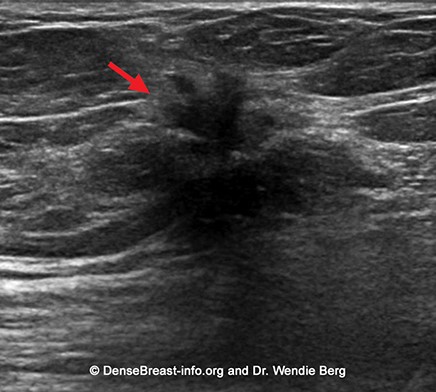

– Siêu âm tuyến vú:

Siêu âm tuyến vú giúp tăng khả năng phát hiện ung thư vú đặc biệt ở những trường hợp có mô vú đặc. Mục đích xác định vị trí, số lượng, tính chất khối u vú, đánh giá tình trạng di căn hạch nách, hạch thượng đòn. Trong trường hợp nghi ngờ, siêu âm giúp định hướng chọc hút tế bào, sinh thiết u vú, hạch để chẩn đoán bệnh